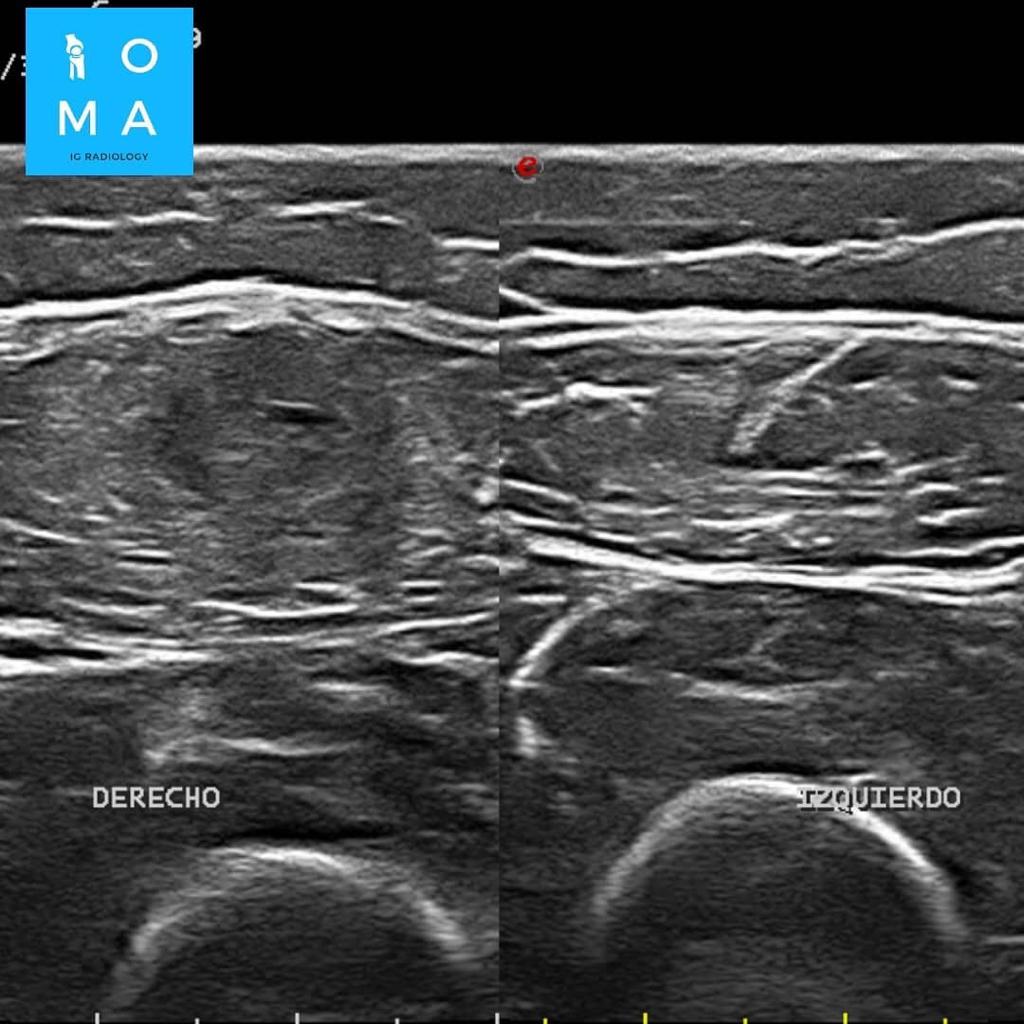

🔹Varón de 12 años que consulta por tumefacción en región anterior de muslo derecho. Refiere molestia a ese nivel 3 días antes, después de pique en partido de fútbol.

🔹Cambios inflamatorios asociado a edema y banda líquida que rodea a la unión miotendinosa central del sector medio del músculo recto anterior del cuádriceps derecho, de 10 mm de extensión, evocador de desgarro de la unión miotendinosa grado II.

🔹En un segundo tiempo se realiza ecografía dirigida, confirmando los hallazgos a nivel del tendón central del músculo recto

anterior del cuádriceps derecho, presentando desgarro grado II, asociado a un

aumento del flujo vascular al examen Power doppler.